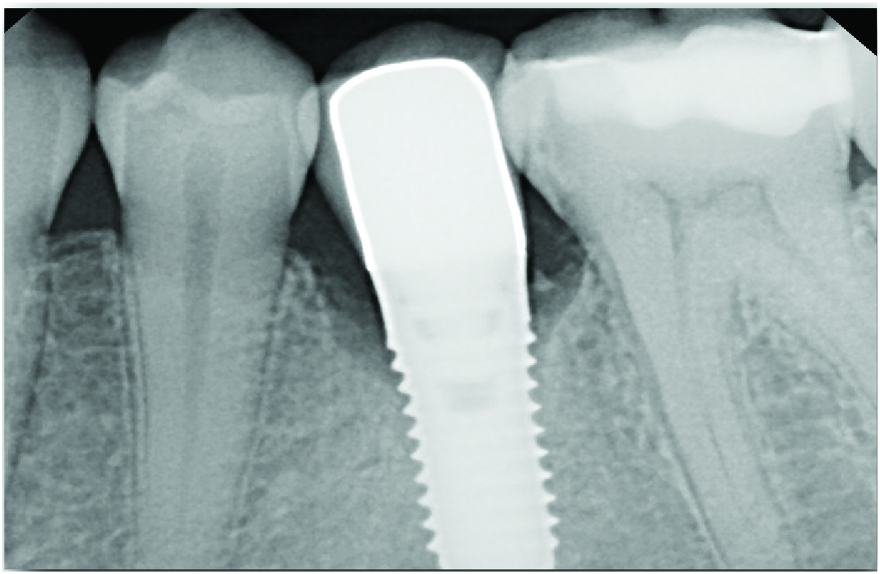

At 5 years post-implant placement, implant site No. 20 showed circumferential depths of 6 mm to 8 mm with heavy bleeding on probing (Figure 1).1,47 The keratinized mucosa width locally recorded 4 mm buccally and lingually, with a thick gingival phenotype. The four-wall intrabony lesion was diagnosed as a class 1c (circumferential) intrabony peri-implant defect with less than 40% defect angulation in the mesial and distal radiographic aspects (Figure 2).48 Additionally, resin cement-associated peri-implantitis was diagnosed.49 The patient preferred to maintain the existing well-fitting crown due to financial concerns. The patient would be considered low-medium risk according to the PIDRA (Table 3). (To view Table 3, the PIDRA for this case, visit compendiumce.com/go/2505.)

A postsurgical periapical x-ray was taken (Figure 9). Postoperative visits were at 2- to 3-week intervals. The patient was instructed to use chlorhexidine for 2 weeks, followed by the use of a two-row soft toothbrush and interproximal flossing. Interproximal proxy brush usage began after the suture removal at 4 weeks. After 2 months, healing was excellent (Figure 10); at 9 months, the interproximal papillae regeneration was complete, and radiographic confirmation of radiographic intrabony defect fill was observed (Figure 11 and Figure 12). After 1 year, maintenance visits were conducted by the restorative office's registered dental hygienist.

Fig 2. A radiograph of the dental implant area before treatment depicted the defect angle, which was less than 40%.

Figure 2

Fig 9. Immediate postoperative radiograph.

Figure 9

Fig 11. Radiograph at 9-month follow-up showing intrabony defect fill.

Figure 11